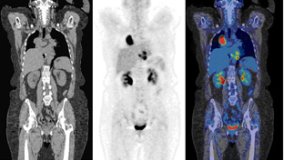

PET/CT Clínico

PET/CT Clínico,? Flujo de trabajo y protocolos clínicos,? Artefactos y Variantes Normales?

PET/CT principles

Introduction to cyclotrons and radionuclide productionPrinciples of operation for PET/CTRadiation

Practice Guidelines for Clinical Applications of SPECT-CT

This eLearning module provides an up to date, evidence-based and comprehensive overview of practical